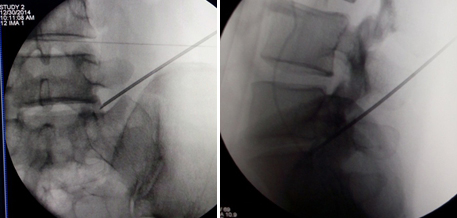

(图)穿刺针定位

(图)置入扩张管

(图)术中